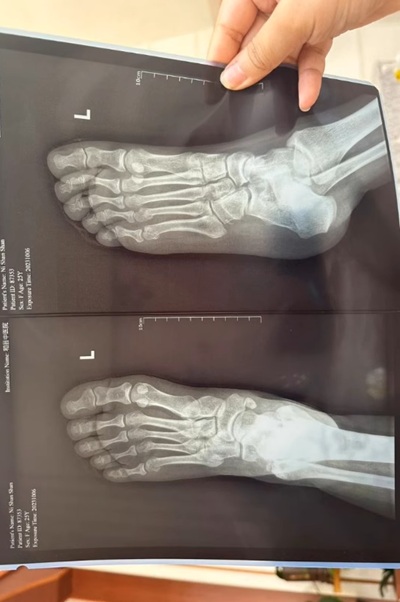

Gout and pseudogout are both forms of arthritis caused by crystal deposition in the joints.

Gout typically affects the big toe (especially the joint at the base of the toe), but it can also affect the knees, ankles, and other joints.